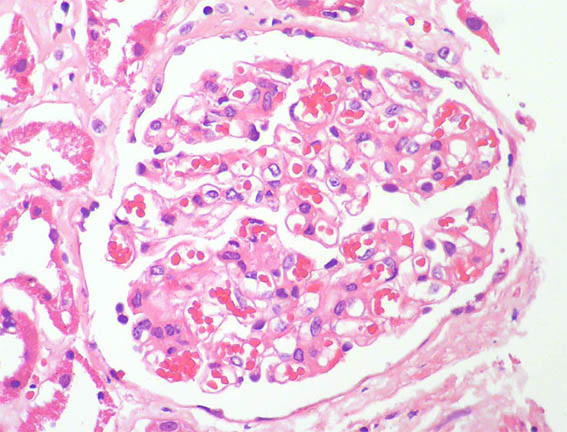

Figure 1. H&E, X100.